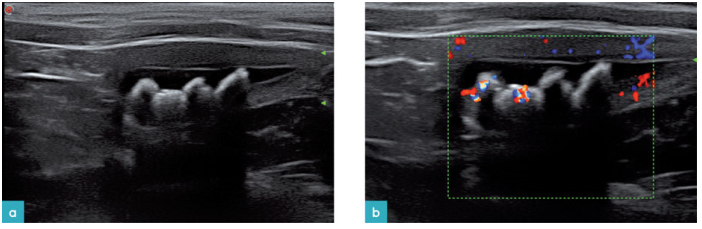

膀胱或输尿管结石通常是圆形的,高回声的,但是它们的大小和形状也是有较大变化的(图15和16)。结石通常位于膀胱的重力面,伴随有声影。但是小结石可能没有声影。

小块细碎结石或细砂样结晶沉积在膀胱的支持面上,会产生线性声影。

当彩色多普勒置于声阻抗差较大的两个界面上(结石与尿液)时会产生闪烁伪影,表现为快速移动的彩色的多普勒信号(图16)。